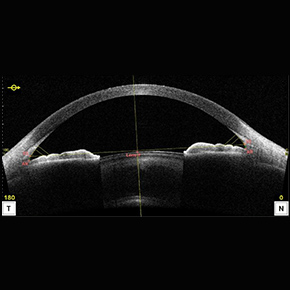

前眼部光干渉断層計(前眼部OCT)

角膜・虹彩・水晶体など前眼部の断層画像を撮影し、隅角(眼の水の流れ道)の状態や角膜形状などから、緑内障や角膜疾患を早期発見